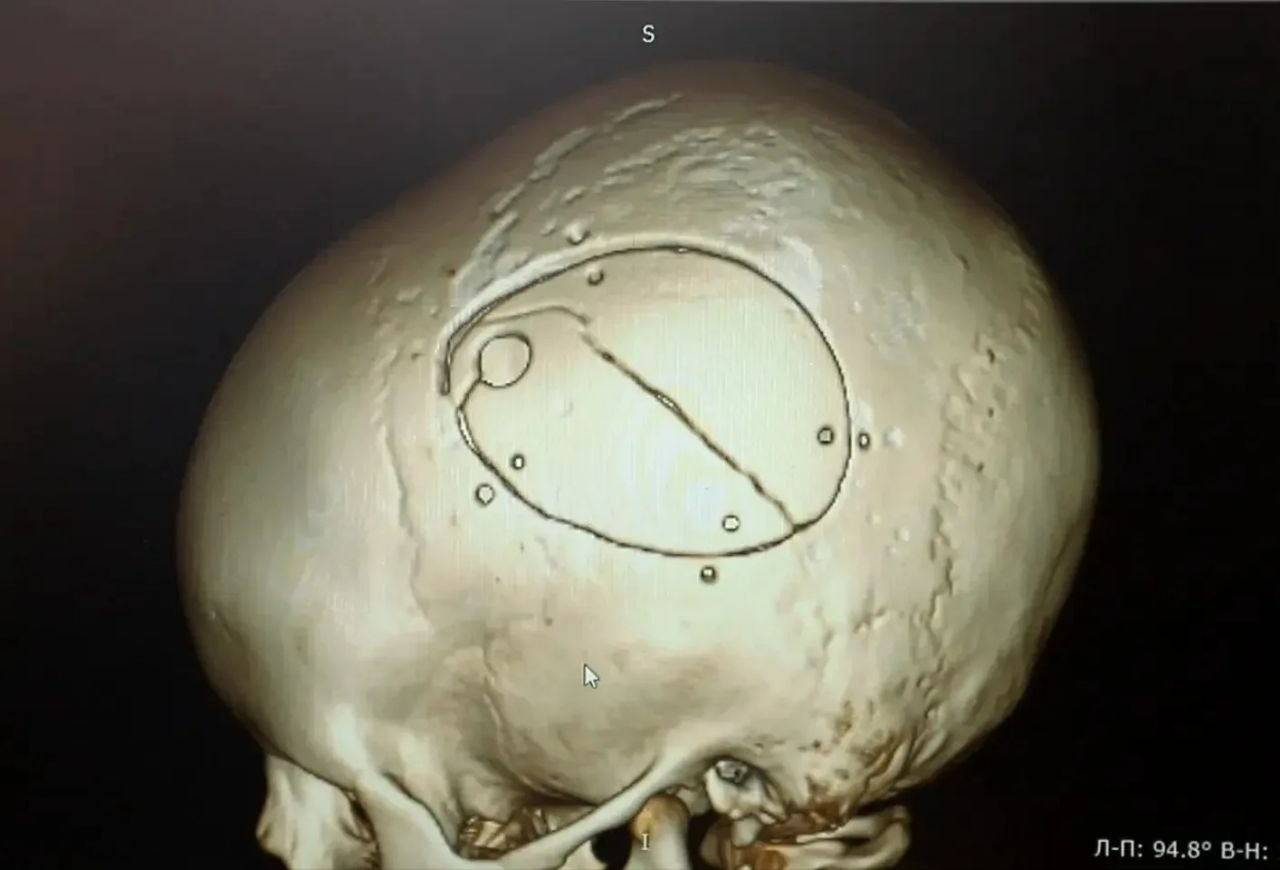

Мальчика экстренно доставили в операционную. Нейрохирурги провели сложную операцию – костно-пластическую трепанацию черепа, удалили гематому и остановили кровотечение.